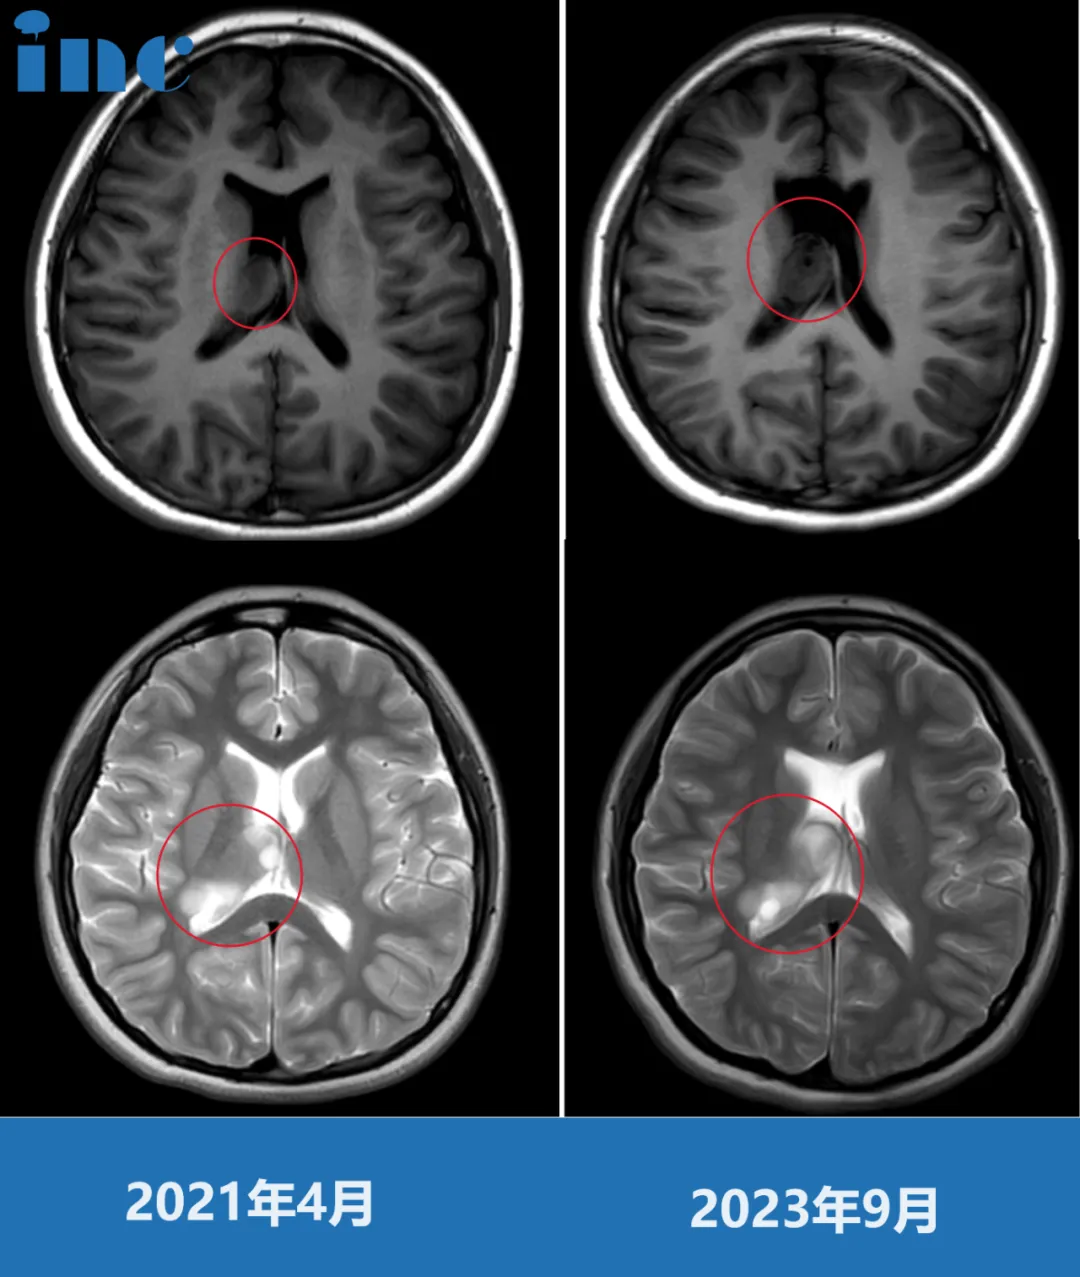

2021年5月,巴教授来华期间,小樱父母就选择与巴教授进行面对面咨询,当时肿瘤还没有进展,因此没有选择手术。

但2023年9月再次面对面咨询时,巴教授这一次再次对比影像,没想到病情进展了……“我研究了现在的影像和之前的影像对比,肿瘤已经变大了,从现在这个情况看,我认为是可以进行手术。而且,肿瘤以一种弯曲特殊的方式在侧脑室中生长。保守并不是个好主意,因为肿瘤会继续生长。手术并不十分紧急,但是这个孩子为什么要等待呢?如果她现在没有症状,这是很好的机会。如果她出现了症状,那么肿瘤已经到了晚期,那就很糟糕了。”